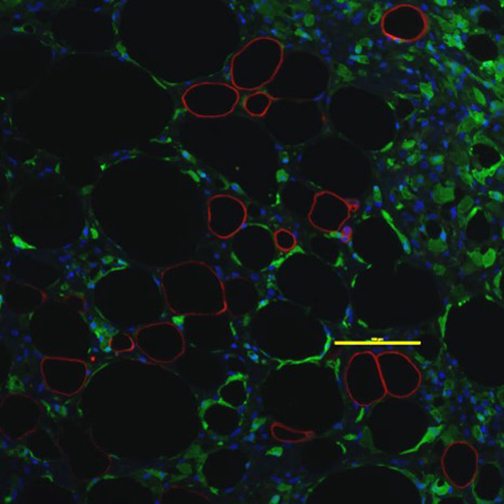

The paper describes a tissue-engineered microstructure called Sandwiched White Adipose Tissue, or "SWAT" for short. White adipose tissue (WAT) is a type of human fat that is strongly associated with several life-threatening illnesses. An ongoing hurdle for scientists has been developing a technique for the long-term culture of WAT. In SWAT, WAT is cultured in a three-dimensional, multicellular environment, and these conditions faithfully mimic those of the human body. In SWAT, WAT is viable in culture for up to eight weeks, and during this time frame, it maintains crucial cellular qualities and whole-tissue functioning.

The research validates SWAT as the first primary human White Adipose Tissue Microphysiological System against standards established by the National Institutes of Health. Its attributes position SWAT as a powerful tool for the study of WAT physiology, pathophysiology, personalized medicine, and pharmaceutical development.